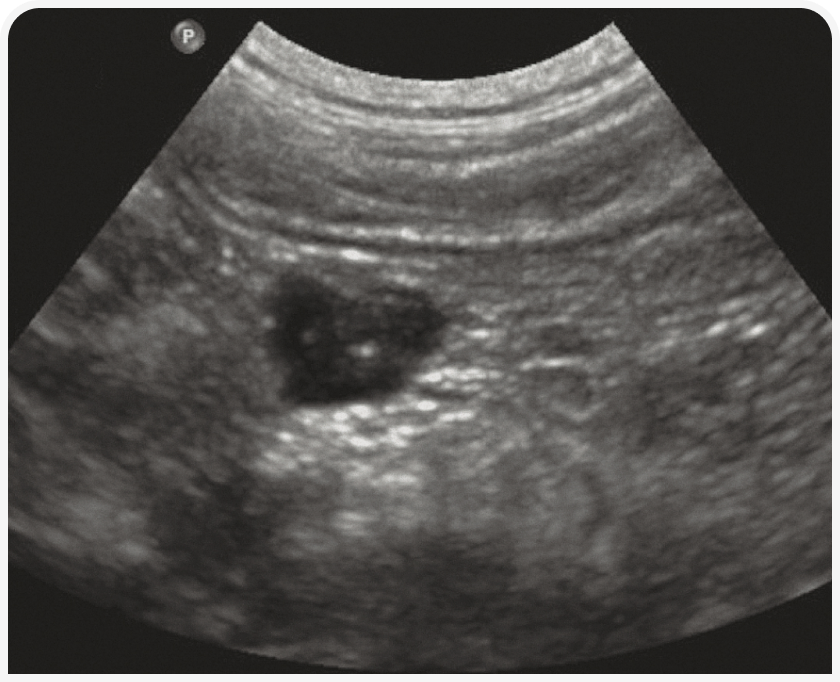

Узловая гиперплазия обычно наблюдается у пожилых кошек и характеризуется гипоэхогенными четко отграниченными узелками диаметром менее 1 см (6). Опухоли поджелудочной железы обычно гипоэхогенные и слегка неоднородные, искажают контуры поджелудочной железы (Рисунок 8). Рак поджелудочной железы часто сопровождается канцероматозом, характеризующимся накоплением жидкости в брюшной полости и диссеминацией гипоэхогенных узелков внутри брыжейки и по брюшине.

Инсулиномы обычно проявляются мелкими гипоэхогенными узелками; визуализировать их иногда оказывается трудно. Часто раньше первичной опухоли обнаруживаются метастазы в печени или прилежащие лимфатические узлы.